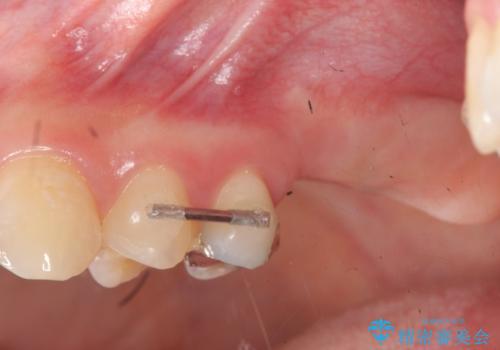

- 「銀歯で被せた歯の歯ぐきが腫れる、痛みが続く。」と痛みの改善を求めて来院されました。

X線検査の結果、左上6には歯根破折、左上7には銀歯の下に大きな虫歯の再発が認められ共に抜歯をせずには症状の改善が見込めない状況です。